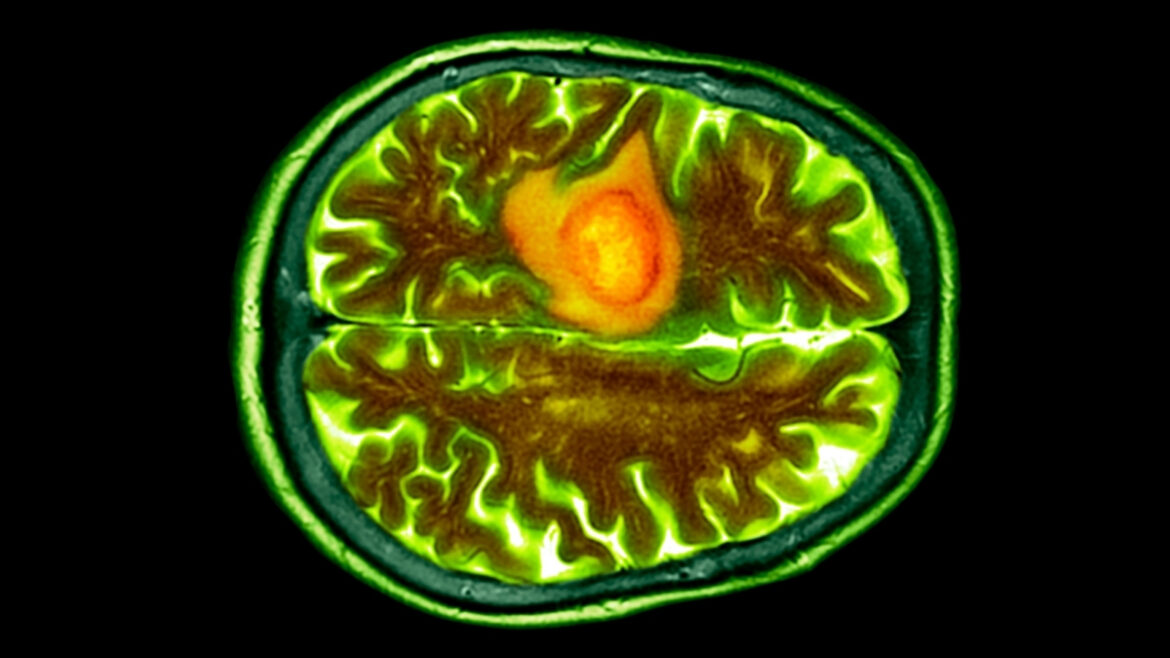

Глиобластома опасна тем, что растёт агрессивно, её трудно обнаружить рано, а также она умеет «выключать» обычный иммунный ответ. Кроме того, до опухоли сложно добраться: она находится в мозге или рядом с другими структурами центральной нервной системы. Опухоль нарушает работу мозга, вызывая отёк, сдавливая здоровые ткани и ухудшая их кровоснабжение.